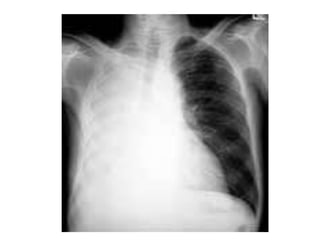

• #51 Paciente masculino de 63 años que refiere tos, disnea y dolor torácico derecho de aproximadamente siete días de evolución. El examen físico revela hipo ventilación en hemitorax derecho. Como dato positivo de laboratorio presenta VSG aumentada. Se solicita inicialmente una radiografía de tórax frente en la cual se observa, radioopacidad basal derecha con broncograma aéreo que borra el seno costofrénico homolateral. Engrosamiento pleural difuso que impresiona comprometer pleura mediastínica. Dados los hallazgos en la radiografía se decide ampliar el diagnostico solicitándole una TAC de tórax con contraste endovenoso en la cual se observa engrosamiento circunferencial pleural de hemitorax derecho. Atelectasia de segmentos inferiores con broncograma aéreo. Pequeña área líquida tabicada. Adenomegalias mediastinales en región prevascular, pretraqueal retrocavo y ventana aortopulmonar. Caja torácica sin alteraciones tomográficamente demostrables. Estructura y densitometría osteoarticular de l raquis dorsal normal. DIAGNOSTICOS DIFERENCIALES: • Engrosamiento pleural: Derrame organizado, hemotórax, piotorax, cirugía previa, radioterapia, exposición al Asbesto. • Tumores Benignos: lipomas, tumores fibrosos, esplenosis torácica. • Tumores malignos: MTTS de pulmón, mama, linfoma. • Mesotelioma maligno. DIAGNOSTICO DEFINITIVO: • MESOTELIOMA MALIGO